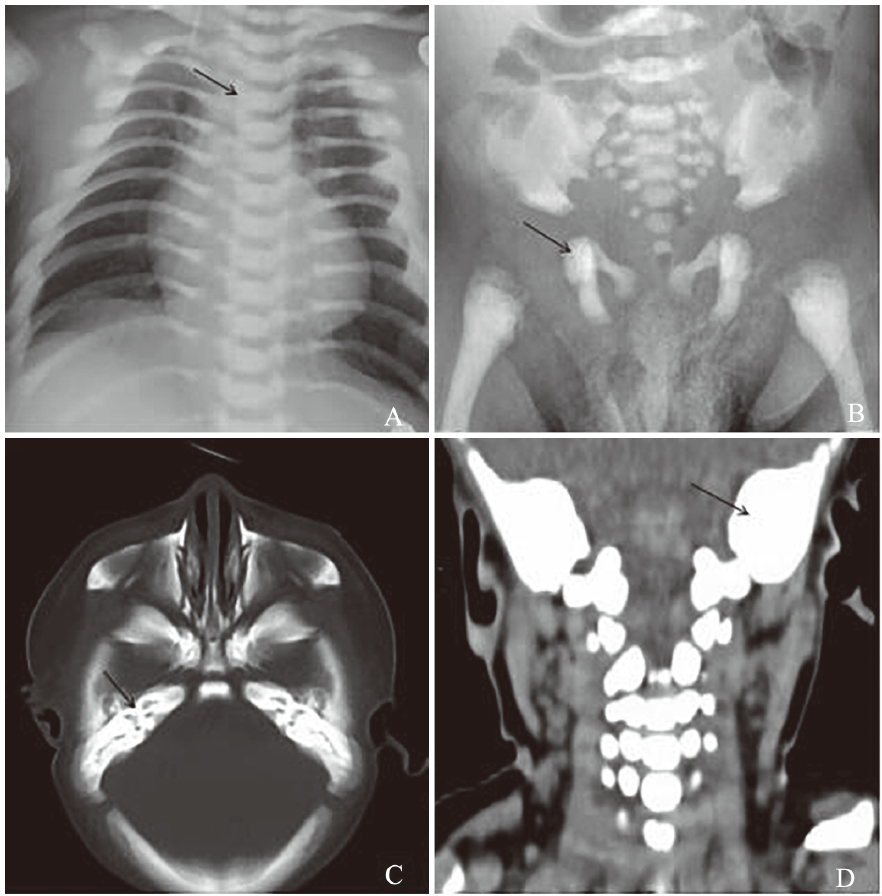

Infantile malignant osteopetrosis (IMO) is mainly manifested with the increased bone density, smaller bone marrow cavity and severe extramedullary hematopoiesis. At present, hematopoietic cell transplantation represents the only curative treatment for IMO. In this article, we reported a 3-month-old male infant with IMO. He was admitted due to abnormal hemograms for 10 d at 9 d after incarcerated right oblique inguinal hernia surgery. Clinical manifestations mainly included inspiratory dyspnea, hepatosplenomegaly and decreased levels of hemoglobin and platelets. Thoracic and pelvic X-ray examination and CT scan of head and neck revealed increased bone density. High-resolution clinical exome sequencing detected homozygous mutation of c. 1480delC (p.Q494Sfs*34) in the T-cell immune regulator 1(TCIRG1) gene, which has not been reported yet. Sequencing data showed that this mutation was inherited from his parents (heterozygous status in his parents, his parents were cousins).